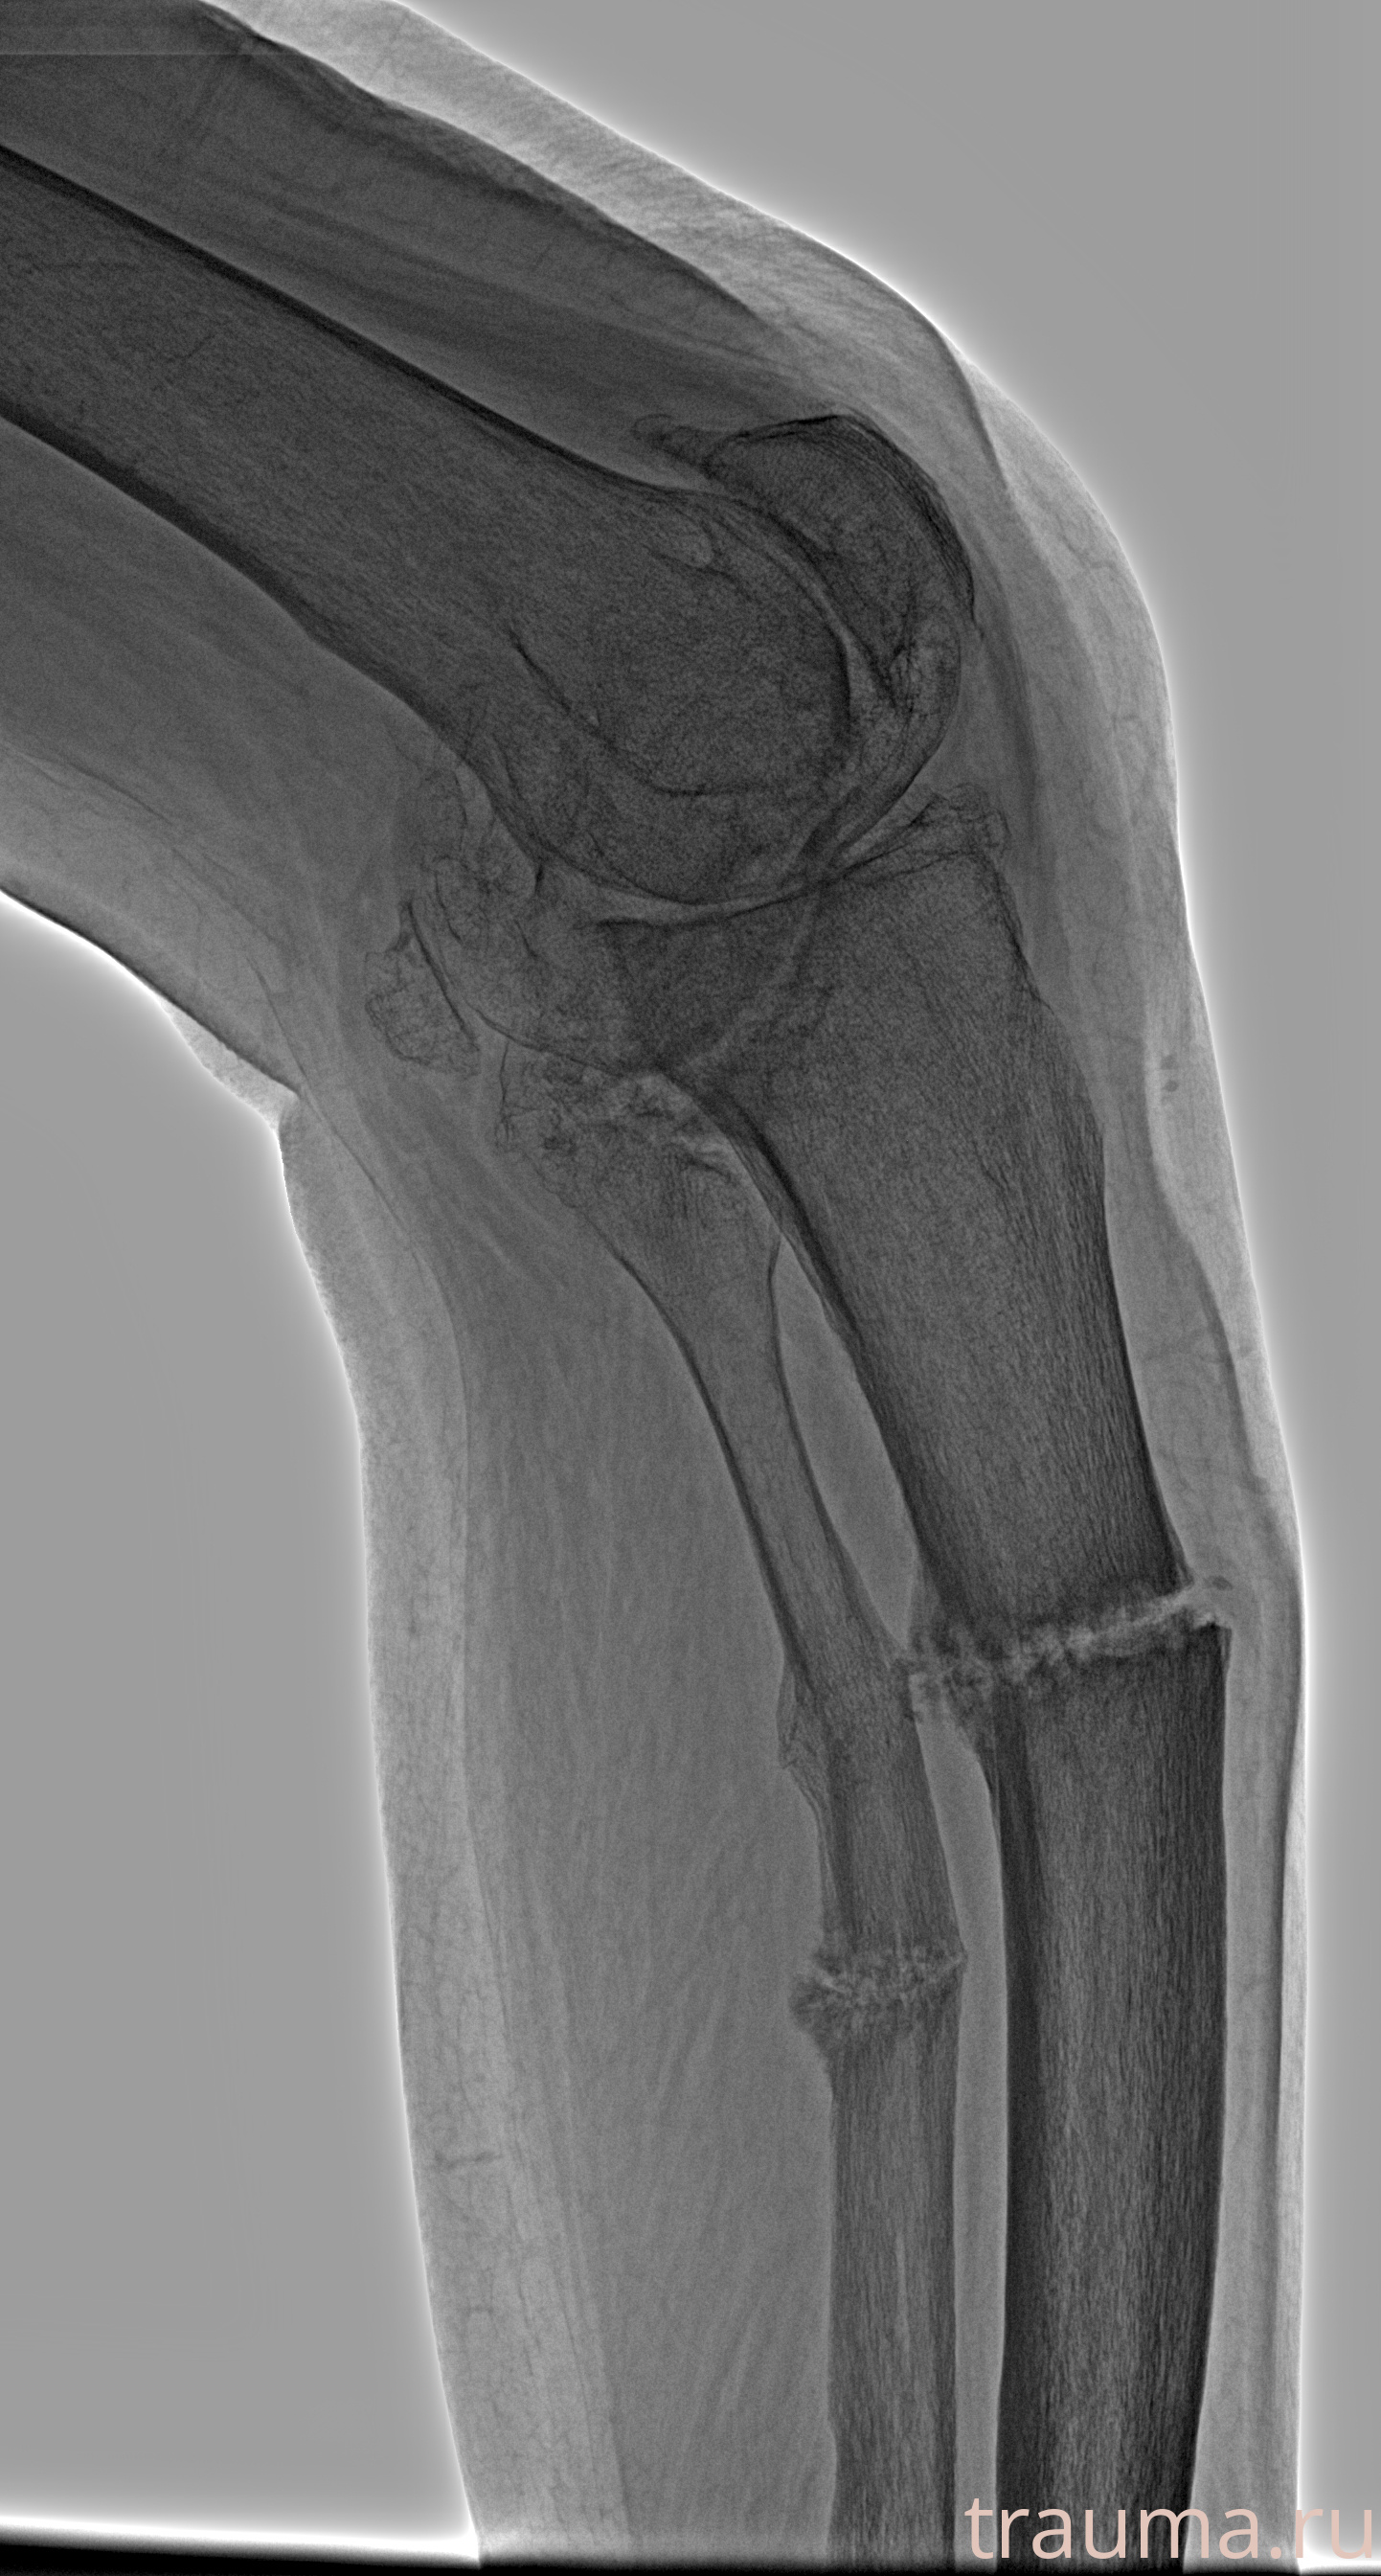

Рентгенограммы

Рентген на дому: по вашему адресу приезжает врач-рентгенолог, травматолог-ортопед с мобильным рентгеновским аппаратом, проводит диагностику травмы или заболевания, делает необходимые рентгенограммы, дает рекомендации по дальнейшему лечению. Получить качественные снимки в домашних условиях возможно благодаря уникальной методике, разработанной МосРентген Центром для института  Склифосовского